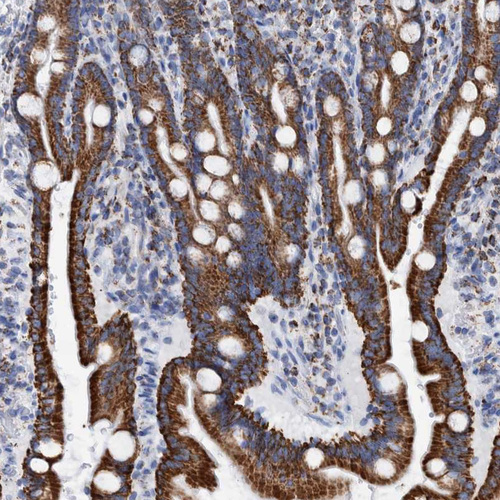

Immunohistochemistry analysis in human liver and placenta tissues using HPA023238 antibody. Corresponding DECR1 RNA-seq data are presented for the same tissues.